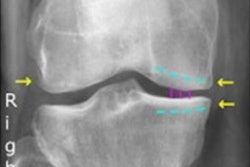

Globally, 178 million fractures were registered in 2019, and missed fractures account for a vast majority of diagnostic errors in emergency settings. RBfracture covers the entire appendicular skeleton and can act as an extra pair of eyes in emergency departments, Radiobotics said.